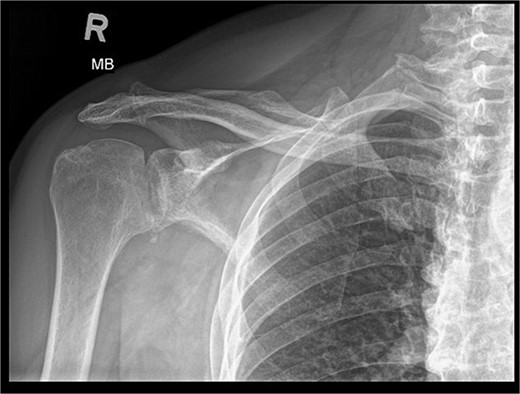

Patient is a 67-year-old male who participated in a road accident on 28 April 2020. As a result of the accident, the motorcycle driver suffered a direct injury to his right shoulder. Immediately after this event, the patient was transported, diagnosed, and treated in the Emergency Ward, where shoulder contusion was diagnosed.

X-ray images can be found in Figs 1 and 2.

After the diagnosis at EW, the decision was made to pursue with the conservative treatment.